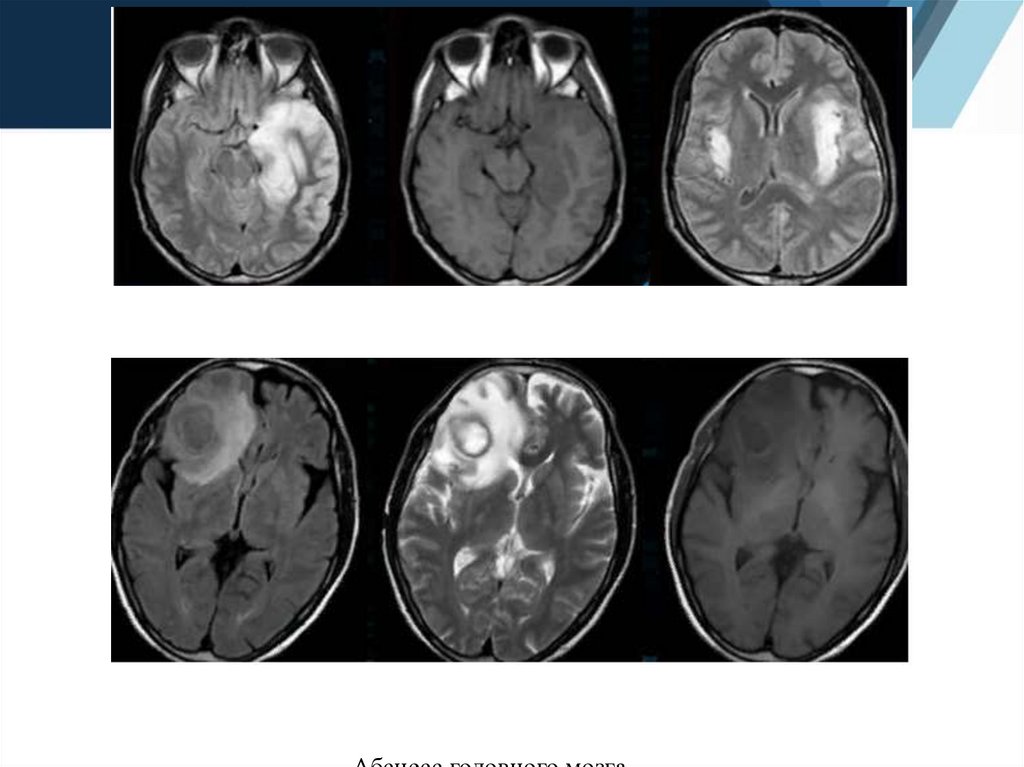

6.

Герметический энцефалит